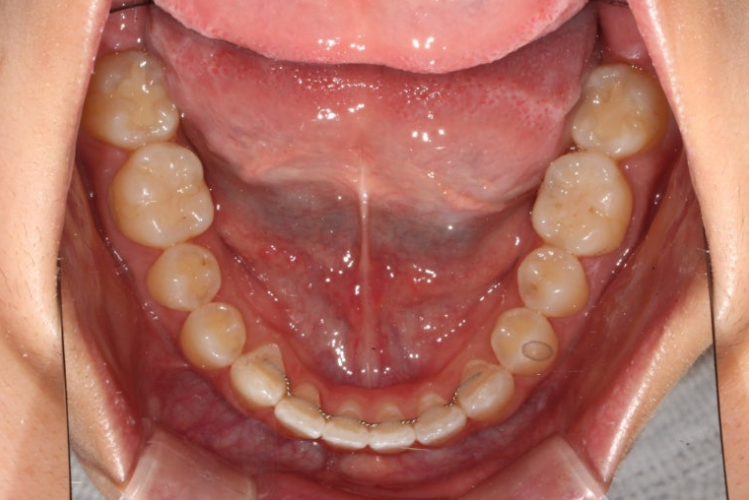

하지만 아래는 철사가 떨어진 부분도 없고 떨어진적도 없습니다. 철사가 붙어 있는 상태에서 철사 자체의 변형으로 치열이 틀어지는 경우가 있습니다. 와이어신드롬 이라고 합니다.

골격 분석시 정상과 주걱턱의 경계에 있는 골격관계라 이미 지금도 턱끝이 좀 도드라져 보이는 편 입니다.

어금니 함입을 통해 개방교합을 해소하면 하악골 자가회전에 의해 처음보다도 턱끝이 더 도드라져 보이게 됩니다.

재교정이라 간단한 치료를 원하셔서 앞니 부분교정으로 개방교합을 해결하기로 합니다.